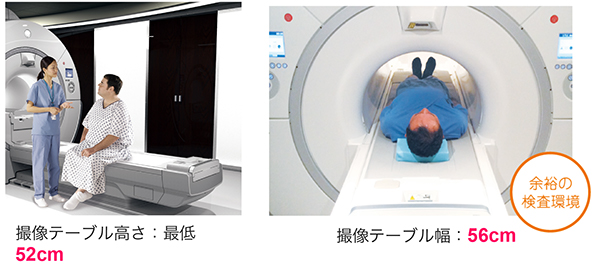

患者入室から退室までをよりスムーズに

・「ワイドテーブル 56cm & ローテーブル 52cm」により,患者入室から退室までをよりスムーズに。